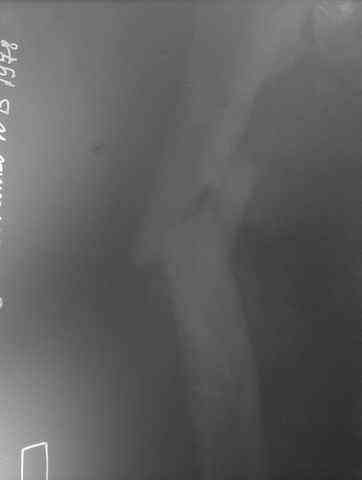

Несрошийся открытый фрагментарный,оскольчатый,перелом в/с/3 правого бедра |

Несрошийся открытый фрагментарный, оскольчатый, перелом в/с/3 правого бедра с размозжением мягких тканей. Состояние после ПХО,МОС,ВО ЧКФ стержневым АВФ. 10.10.09.Заживление раны per prima. Операция:16.12.09,открытый накостный МОС,аутокостная пластика(из крыла подвздошной кости)правого бедра. После п/о периоде заживление раны вторичным натяжением (на 5-е сутки распущены швы, после очищения раны наложины вторичные швы) На этапных RO-гр:остеолизис костного трансплантата и дистального фрагмента перелома бедра. Вопрос:дальнейшая тактика лечения-БИОС аутокостная пластика (трансплантат на сосудистой ножке М/Б кости). Билокальный остеосинтез по Илизарову с остеотомией подвертельной и надмыщелковой области бедра. Мозможен ли аутотрансплантат без сосудистой ножки? Чем улучшить васкуляризацию? Декортикация? Тактика выжидания остеолизиса, а затем оперативное лечение.